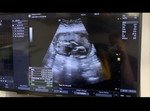

เดือนที่แล้วซาวด์ พบถุงตั้งครรภ์ ถ้านับจาก ปจด 11wวันนี้ แต่วันนี้ไปซาวด์ เด็กมีขนาดแค่ 1 ซม. เท่ากับอายุครรภ์ 6w หมอบอก ปจด อาจเคลื่อน แต่ ปจด ไม่มา1 เดือน เราตรวจว่าท้องเลยนะ ตรวจน้องหัวใจเต้นปกติ มีใครเคยเป็นมั้ยคะ เคียดมากว่าทำใมเด็กไม่โต